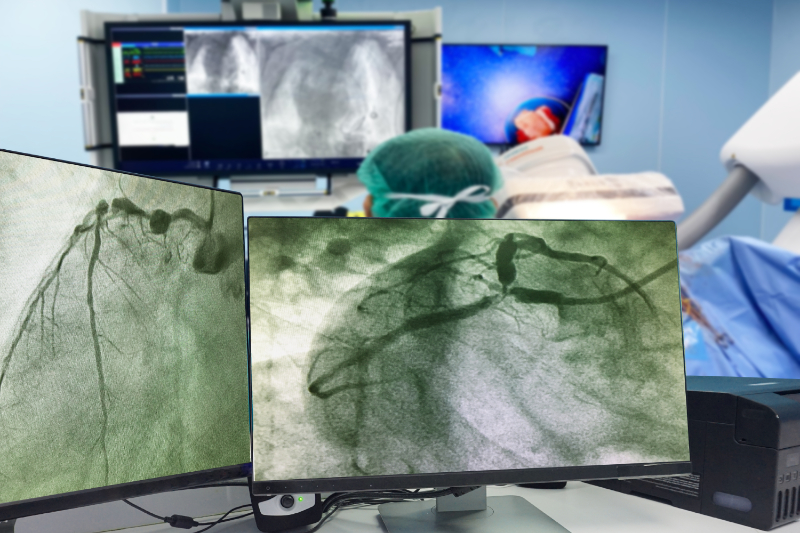

Cardiac catheterization is an invasive procedure that can be utilized as a diagnostic and therapeutic intervention for certain ischemic heart conditions. It plays a critical role in evaluating angina by directly assessing coronary circulation and cardiac function. Typically performed in a specialized catheterization lab under sterile conditions and local anesthesia, the procedure involves the insertion of a flexible catheter into a vein or artery, most commonly in the groin (femoral artery) or wrist (radial artery), and advancing it toward the heart (National Heart, Lung, and Blood Institute, 2022a).

Cardiac catheterization is indicated for a range of clinical purposes, including:

This reduction in blood flow is often associated with the presence of atherosclerotic plaque. These vulnerable plaques are prone to rupture or dislodgement, which can lead to the release of embolic debris that partially blocks a coronary artery. Such partial, non-occlusive obstructions are often detected through coronary angiography or angioscopy and are believed to be the primary cause of unstable angina in most patients (Klabunde, 2023).